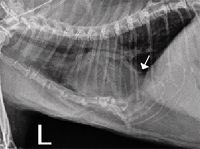

Urolithiasis is common in dogs and cats, causing morbidity and, occasionally, mortality.

This condition often goes unnoticed for years, and many cases are discovered incidentally on radiographs.

In 1981, calcium oxalate was detected in only 2 percent of feline uroliths submitted to the Minnesota Urolith Center, whereas struvite was detected in 78 percent. However, beginning in the mid-1980s, a dramatic increase in the frequency of calcium oxalate uroliths occurred in association with a decrease in the frequency of struvite uroliths (Figure 1) .